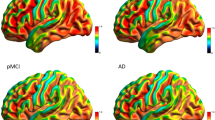

The EC and the hippocampus are among the first regions targeted by AD pathology [38]. However, while several observations suggest that early hippocampal structural brain damage in AD is coupled with hypofunction and specifically reduced brain glucose metabolism, hippocampal hypometabolism is not always evident on PET studies [38]. Conversely, hypometabolism can be found in the posterior parieto-temporal cortex, lateral occipital cortex, precuneus, and posterior cingulate (PC) [9, 29] in various combinations in individual cases. It has thus been hypothesized that decreased posterior parietal and PC activity in prodromal AD (pAD) reflects decreased connectivity especially with the EC and hippocampus [39]. This hypothesis, which fits well with the concept that 18F-FDG PET reflects brain glucose consumption at synaptic level, has been tested and confirmed by two metabolic connectivity studies. In the already mentioned study by Mosconi et al. [20] that a voxel-based correlation analysis of EC indicated an altered functional relationship between the EC and several cortical and limbic regions in AD with respect to normal aging. These results were confirmed using a different approach to metabolic connectivity analysis. Indeed, other authors [37], by means of SICE analysis, demonstrated that compared with normal controls, AD patients show a decrease in the amount of interregional functional connectivity within the temporal lobe, especially between the areas around the hippocampus. Similarly, more recently, in the context of a project by the European Alzheimer’s Disease Consortium (EADC) [22], a metabolic connectivity analysis of both hippocampi was performed in 36 pAD patients and in two independent groups of 36 and 69 age-matched healthy controls. Prior to interregional correlation analysis, the area of hypometabolism in pAD was assessed. This preliminary step aimed to identify regions characterized, or otherwise, by relative hypometabolism in AD with respect to controls. As compared with the controls, the pAD patients showed relative hypometabolism in a large region including the posterior parietal cortex, precuneus, PC in both hemispheres, and lateral temporal lobe in the left hemisphere. Therefore, like previous PET studies, this analysis failed to find significant hippocampal hypometabolism in AD in comparison with controls. Accordingly, the authors specifically aimed to identify impairment of hippocampal metabolic connectivity even in the absence of hippocampal hypometabolism. In both the patient and control groups, extracted normalized mean hippocampal VOI counts were used as covariates to find regions showing significant voxel-wise correlations across subjects according to the procedure validated by Lee et al. [21]. Besides the expected autocorrelation, in both control groups, hippocampal metabolism showed correlations with the temporal, frontal, occipital cortex, and caudate nucleus. By contrast, in pAD patients, metabolism of both hippocampi showed autocorrelation and correlation with both the contralateral one and the amygdala. These findings strongly support the hypothesis that decreased posterior cingulate cortex activity in pAD reflects decreased connectivity, especially with the EC and hippocampus, and indirectly testifies to their damage. Figure 1 shows an example of metabolic connectivity analysis of the left hippocampus in controls and in a group of pAD patients.

Example of the results of voxel-wise interregional correlation analysis of the left hippocampus (HC) in 36 normal elderly control subjects (CTR) (a) and 36 prodromal Alzheimer’s disease patients (pAD) (b). In the CTR, left HC metabolism showed, besides the expected autocorrelation, correlations with the temporal, frontal, and occipital cortex and striatal nucleus bilaterally, while in the pAD, HC metabolism showed only autocorrelation and correlation with contralateral homologous HC